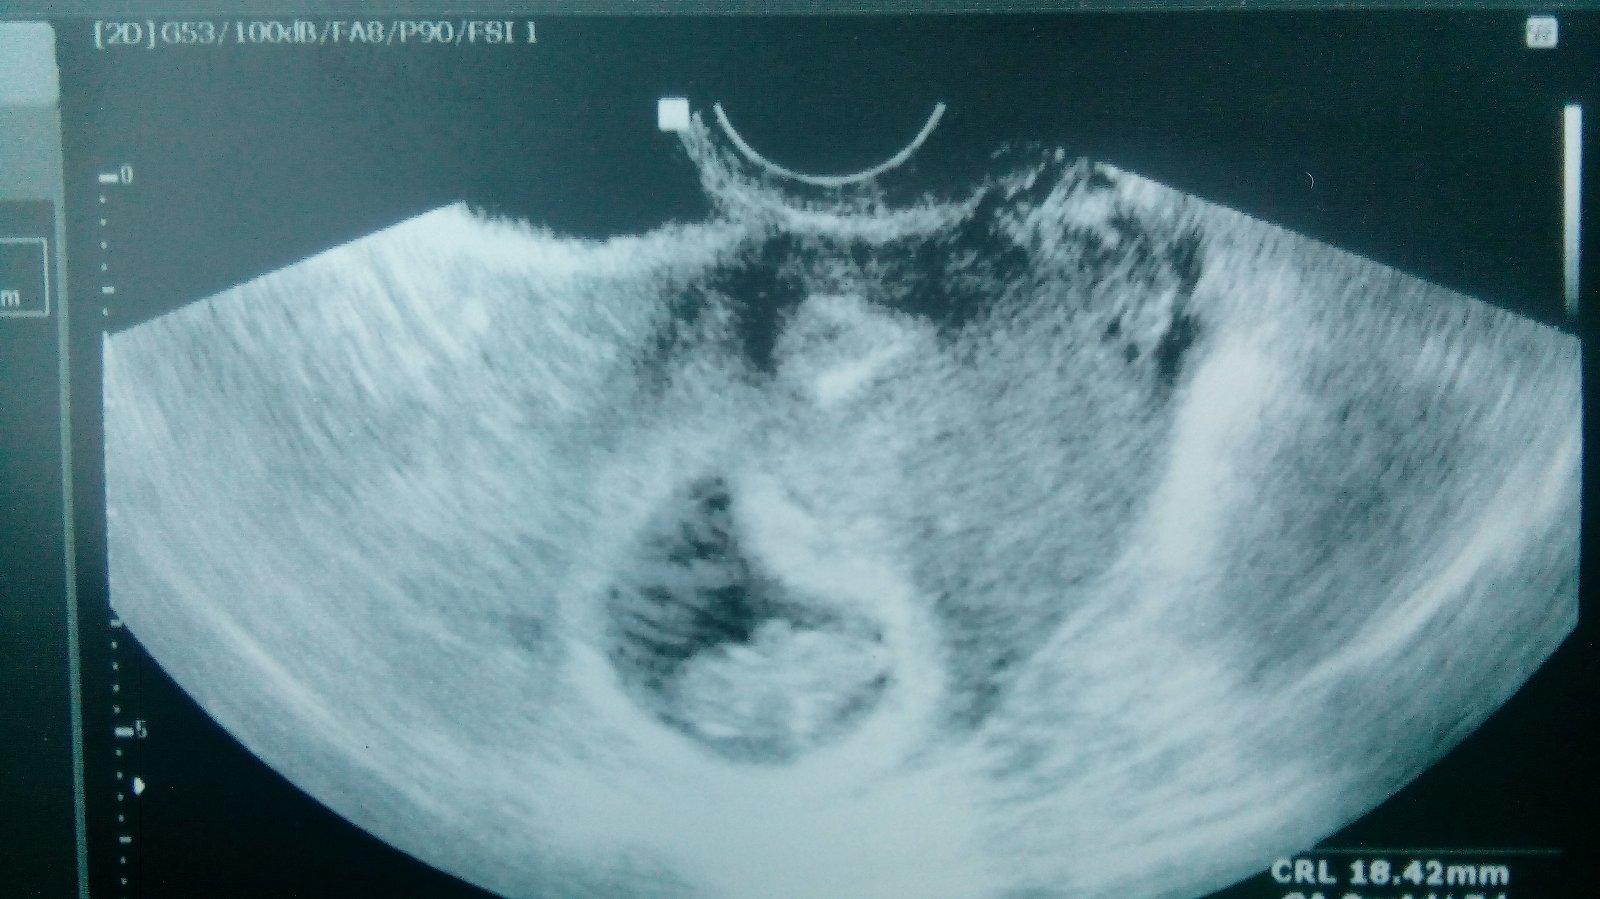

@priefi a jinak dekujem zatim vsechno je v poradku 🙂 posilam fotexku jak jsme krasne vyrostli 🙂

@luciek9152 Krasna fotecka 😊 Ty prirovnani se budou menit 😊 pristi kontrolu zase bude vypadat jinak. Jak jsem.cekala syna, tak jsem taky nosila fotecky, az byl prilis velky, tak uz to neslo, bylo to hodne rozmazane (dr.asi mel starsi ultrazvuk). Kazdo ko, jsem se tesila na fotku 😊 Je krasne pak pozorovat, az bide vetsi, jak se hybe 😊 a ve 20tt je velky ultrazvuk a tam muze i manzel 😉 a nechate si rici pohlavi, anebo se chcete nechat prekvapit?